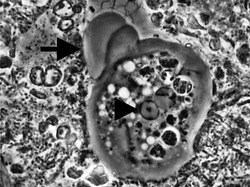

Entamoeba histolytica trophozoite

Entamoeba cells are small, with a single nucleus and typically a single lobose pseudopod taking the form of a clear anterior bulge. They have a simple life cycle. The trophozoite (feeding-dividing form) is approximately 10-20 μm in diameter and feeds primarily on bacteria. It divides by simple binary fission to form two smaller daughter cells. Almost all species form cysts, the stage involved in transmission (the exception is Entamoeba gingivalis). Depending on the species, these can have one, four or eight nuclei and are variable in size; these characteristics help in species identification.

Since E. histolytica does not form cysts in the absence of bacteria, E. invadens has become used as a model for encystation studies as it will form cysts under axenic growth conditions, which simplifies analysis.[8] After inducing encystation in E. invadens, DNA replication increases initially and then slows down. On completion of encystation, predominantly tetra-nucleate cysts are formed along with some uni-, bi- and tri-nucleate cysts.[9]

Uninucleated trophozoites convert into cysts in a process called encystation. The number of nuclei in the cyst varies from 1 to 8 among species and is one of the characteristics used to tell species apart. Of the species already mentioned, Entamoeba coli forms cysts with 8 nuclei while the others form tetra-nucleated cysts. Since E. histolytica does not form cysts in vitro in the absence of bacteria, it is not possible to study the differentiation process in detail in that species. Instead the differentiation process is studied using E. invadens, a reptilian parasite that causes a very similar disease to E. histolytica and which can be induced to encyst in vitro. Until recently there was no genetic transfection vector available for this organism and detailed study at the cellular level was not possible. However, recently a transfection vector was developed and the transfection conditions for E. invadens were optimised which should enhance the research possibilities at the molecular level of the differentiation process.[10][11]